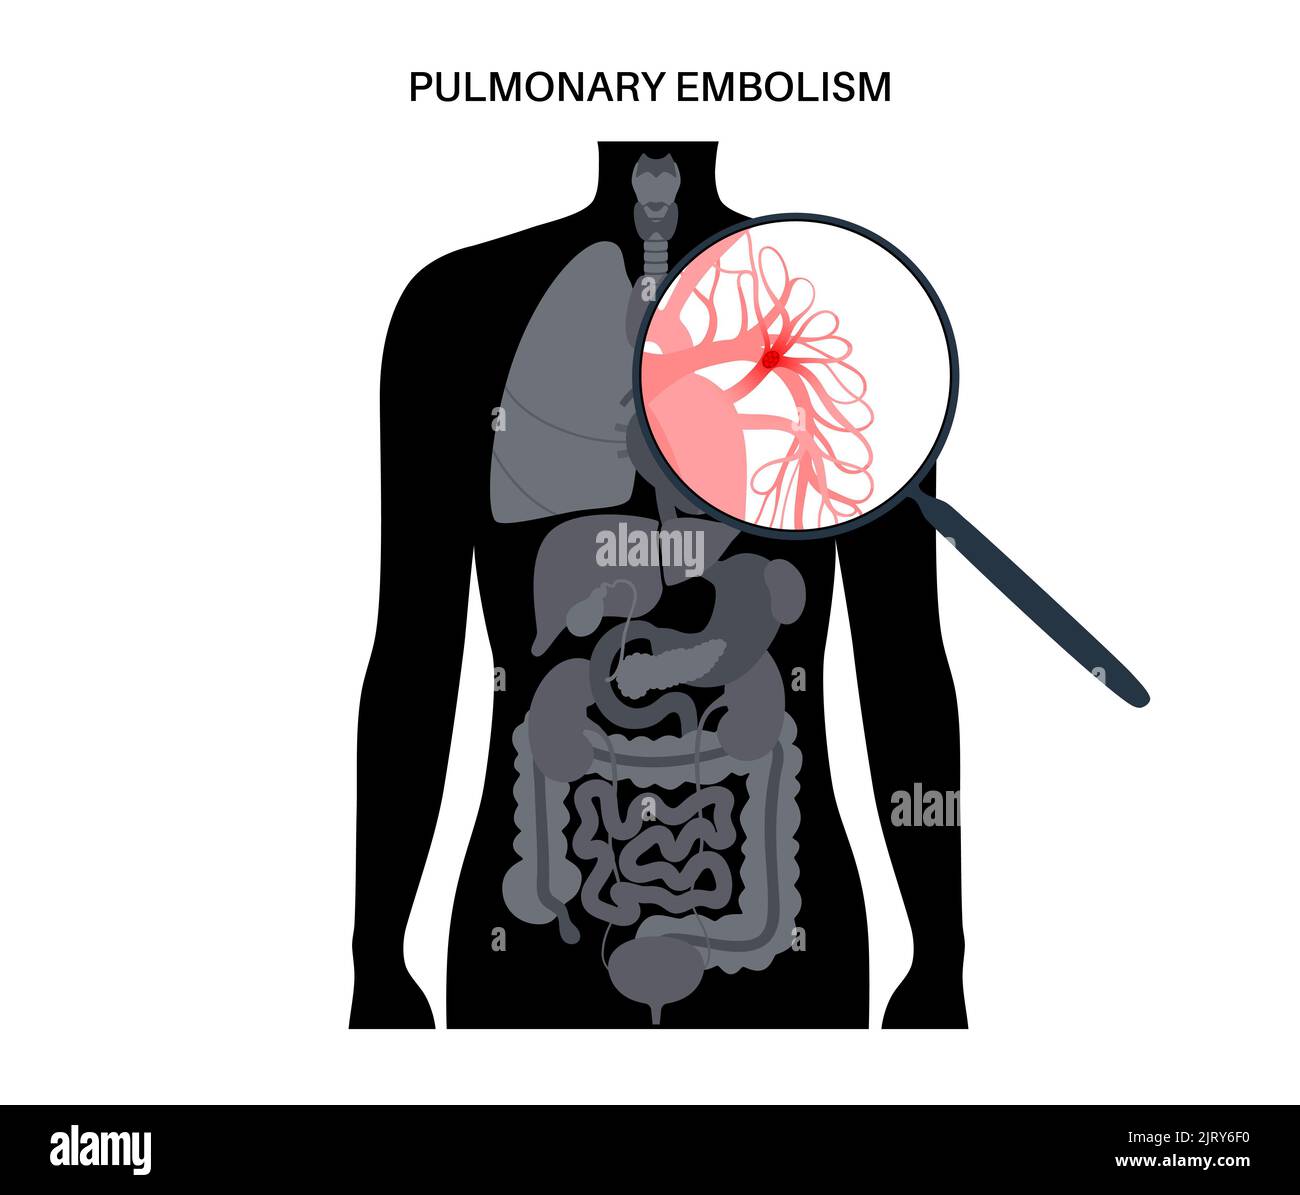

RM2H1FTKC–Syndrome mécanisme, thrombose veineuse profonde ou embolie pulmonaire, thrombose ou PE, thrombose coronaire, illustration du schéma de jambes mâle

RFRN7ABR–Syndrome mécanisme, thrombose veineuse profonde ou d'une thrombose veineuse profonde, embolie pulmonaire, thrombose coronaire, schéma

RFRN7AAX–Syndrome mécanisme, thrombose veineuse profonde ou d'une thrombose veineuse profonde, embolie pulmonaire, thrombose coronaire, schéma